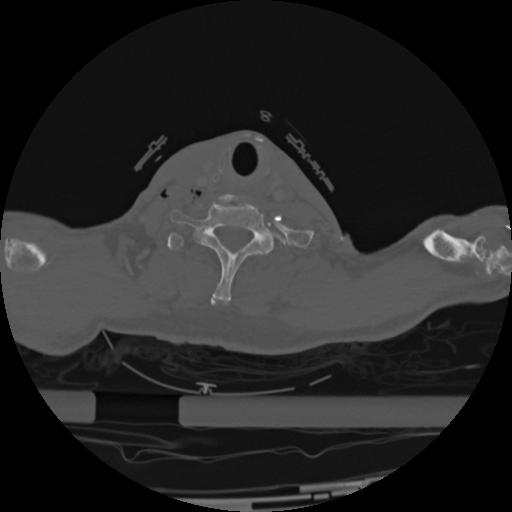

22 ANGIO,CE,Vol,0.5,ANGIO,,